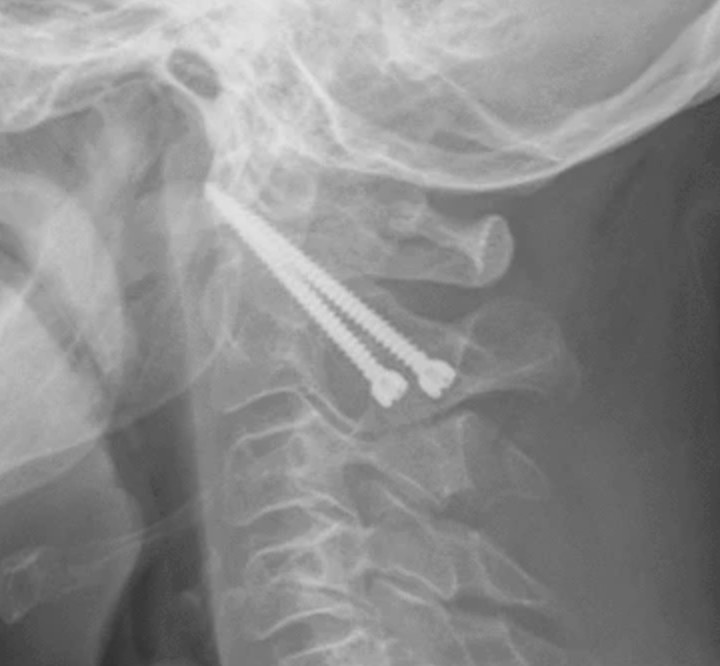

C1/C2 fusion

1. Transarticular screws (Magerl)

2. C1 lateral mass / C2 pedicle screws (Goel-Harms)

+/- Brooks interlaminar wire with posterior bone graft

C1 lateral mass / C2 pedicle screws (Goel Harms)

Transarticular / Magerl screws from: Koepke et al Nature Reports